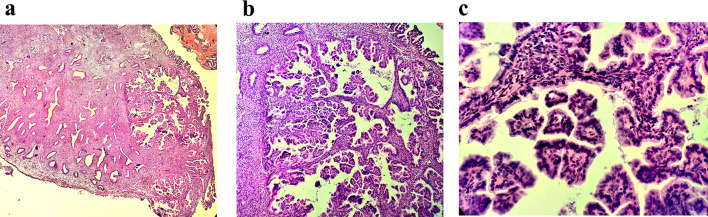

Case presentation: A 49-year-old premenopausal woman presented with irregular vaginal bleeding. Histopathological examination revealed multifocal lesions confined within and on the surface of endometrial polyps, exhibiting complex papillary structures with bland cytology. Immunohistochemistry showed strong ER/PR positivity and retained PTEN expression, while molecular analysis confirmed the absence of high-risk mutations (PTEN, PIK3CA, TP53, CTNNB1).